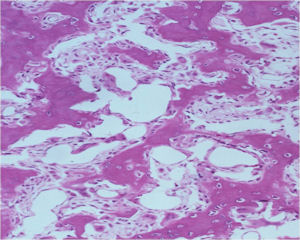

Microscopic Pathology

- Interlacing network of bone trabeculae in a loose fibrovascular stroma

- Prominent vessels

- Osteoblasts are plump, active, scattered mitotic figures

- Osteoblasts line up around periphery of trabeculae (Osteoblastic Rimming)

- Soft tissue component usually surrounded by shell of reactive bone or periosteum (Egg Shell Rim of Calcification)

- No cartilage production (as opposed to osteosarcomas that may contain areas of cartilage)